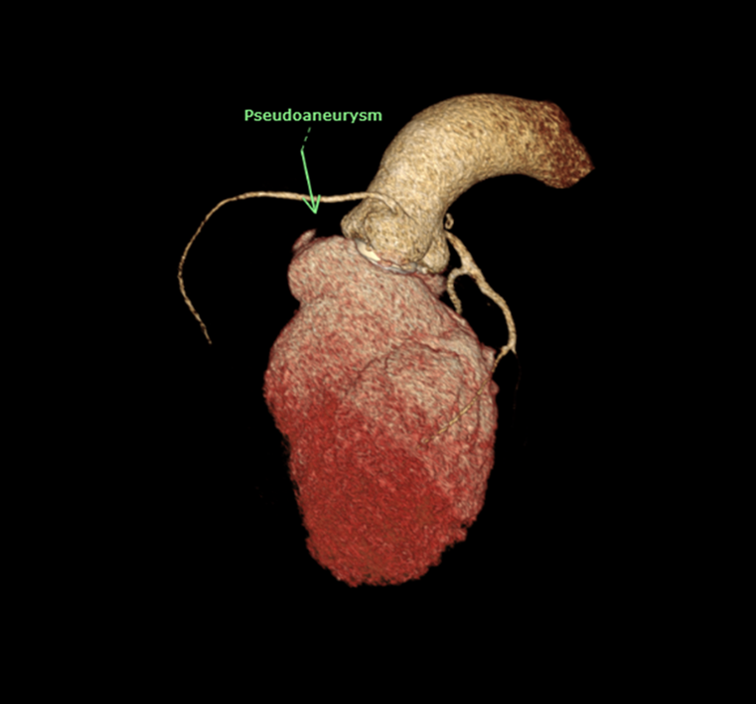

EKG showed normal sinus rhythm with ST segment elevation at V1-3 , inverted T wave at V4-6 , I ,aVL. Echocardiogram showed impaired LV systolic function, global wall hypokinesia, normal prosthetic aortic valve function with mild paravalvular leakage and bulging of aortomitral intervalvular fibrosa, suspected Aortomitral intervalvular fibrosa aneurysm. CT cardiac revealed pseudoaneurysm of the aortomitral intervalvular fibrosa with laminated thrombus with no LAA thrombus visualized.